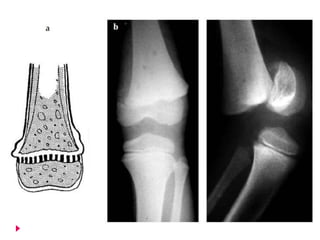

   Clasificación de Salter y Harris

   Tipo I (6%)  Decolamiento epifisiario   *Despegar

   En una lesión de la placa epifisaria tipo existe una separación

completa de la epífisis con respecto a la metáfisis sin fractura

ósea.

   Las células en crecimiento de la placa epifisaria permanecen en

la epífisis.

   Este tipo de lesión, causada por una fuerza cizallante o por

avulsión, es más frecuente en el momento del parto y durante la

primera infancia, cuando la placa epifisaria es relativamente

gruesa.

   También se observa en desprendimientos patológicos

asociados con raquitismo, escorbuto, osteomielitis y trastornos

endocrinos.

   Es raro observar amplios desplazamientos, porque las

inserciones periósticas permanecen intactas.

   La reducción no es difícil, y el pronóstico con respecto al

crecimiento futuro es excelente, a menos que la epífisis